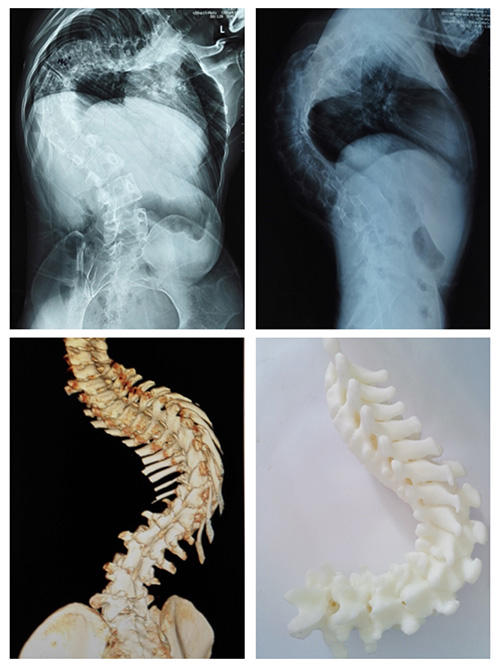

案例一:患者陶某,女,23岁,宣威市某幼教机构教师,于2006年(12岁)就开始出现双侧肩背部不等高,且逐年加重。她曾在家乡县医院就诊,被告知当时并无合适的治疗技术,只好回家任病情继续发展,有时做些针炙理疗等治疗,但效果并不太好。陶某上学时还能坚持进行体育运动,近年她同事发现她走路时有“喘息”声,提醒她最好再去医院看看。陶某虽然自己没发觉有不适,适逢了解到现在已有手术方式可以治疗此病,她决定来到少妇色情 进行手术治疗。

入院后,医生对她进行术前检查,发现陶某侧弯较重,侧弯Cob角达140°,后凸Cob角达105°。